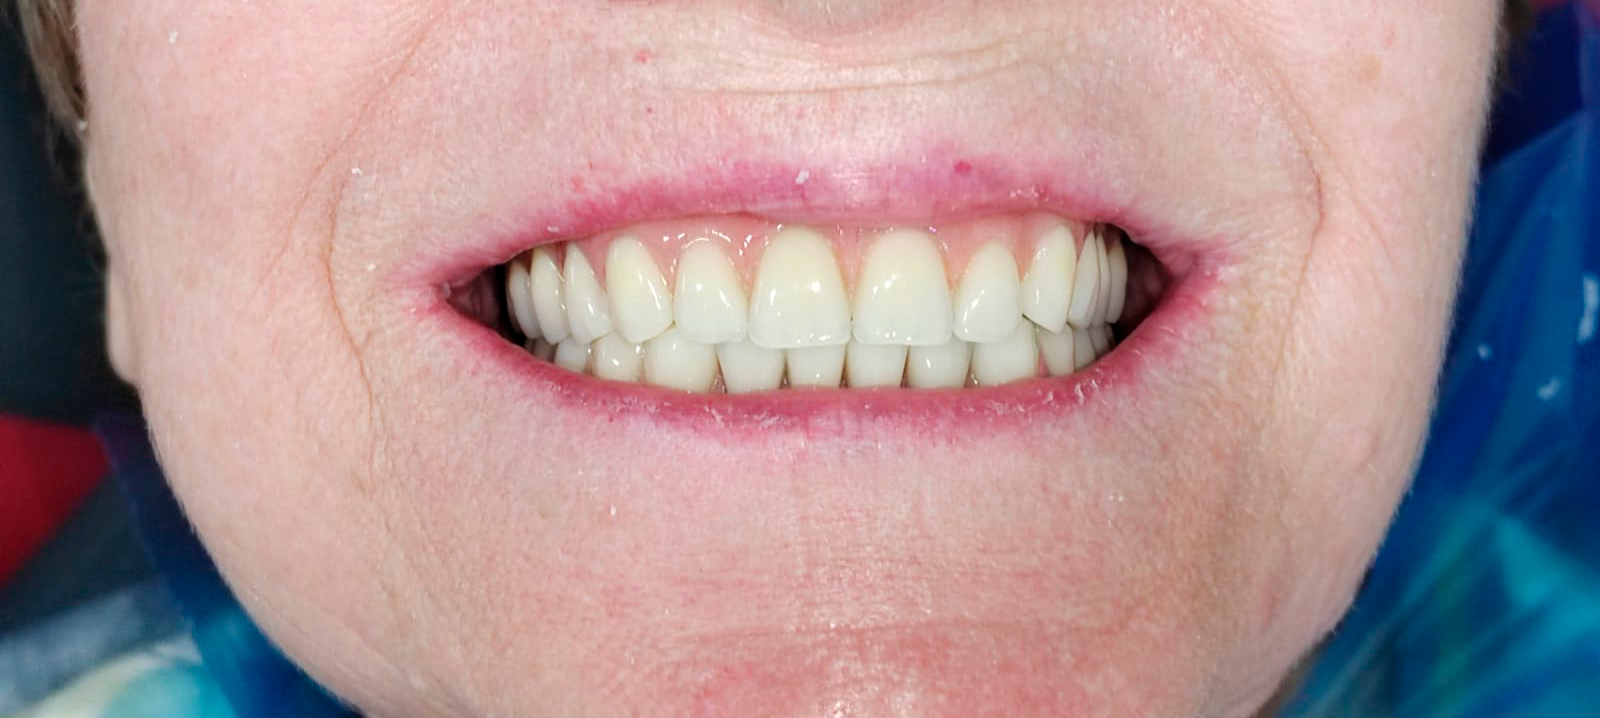

Временные композитные реставрации. Промежуточный этап в ортопедическом лечении. Выполнил врач Краснов Д.А.

После